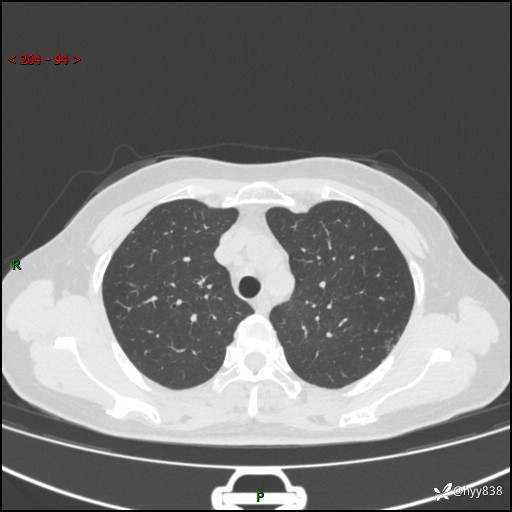

【患者信息】:58岁/女

【主诉】:体检发现肺结节

【检查】:胸部CT平扫+增强